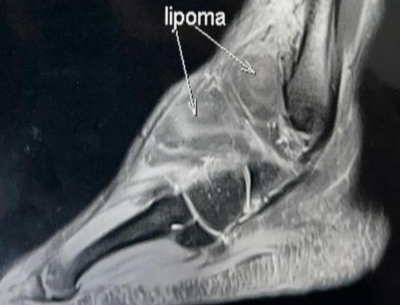

Beyond The Sprain, Unmasking a Rare Anterolateral Ankle Pathology in a Young Athlete

Girish Motwani , Shubham Kalnawat , Khanjan Ahir , Kanishk Bhandari

………………………………p.225-229